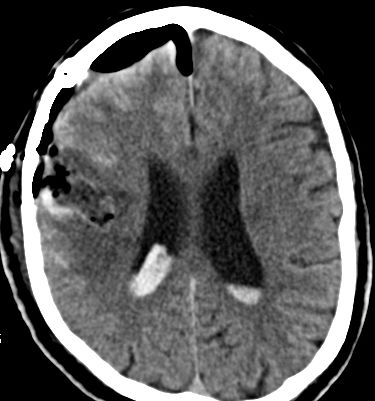

CT Bildgebung der klassischen subarachnoidalen Blutverteilung nach SAB

Als schnellste und sicherste Maßnahme gilt das craniale Computertomogramm (CCT). Hier lässt sich eine frische SAB meist zuverlässig darstellen, wobei auch bereits richtungsweisende Befunde, wie das Ausmaß der Blutung und eine eventuelle Lokalisation eines möglichen Aneurysmas bestimmt werden können. Darüber hinaus kann ein Angio-CCT, bei dem zusätzlich Kontrastmittel verabreicht wird und dann die intrazerebralen Blutgefäße gesondert rekonstruiert und dargestellt werden, weitere Informationen liefern. Der sogenannte “Goldstandard” zur Diagnose zerebraler Gefäßmissbildungen ist jedoch die zerebrale Angiographie. Dabei wird mit Hilfe eines speziellen Katheters über die Leisten- oder Armarterie Kontrastmittel gegeben und die zerebralen Blutgefäße hoch selektiv dargestellt. Sollten sich auf dem initialen CCT Zeichen des Hirnwasseraufstaus zeigen, der durch ein Verstopfen der Abflusskanäle durch das neu aufgetretene Blut bedingt ist, ist oft die Anlage einer Hirnwasserableitung nach außen notwendig (externe Ventrikeldrainage).